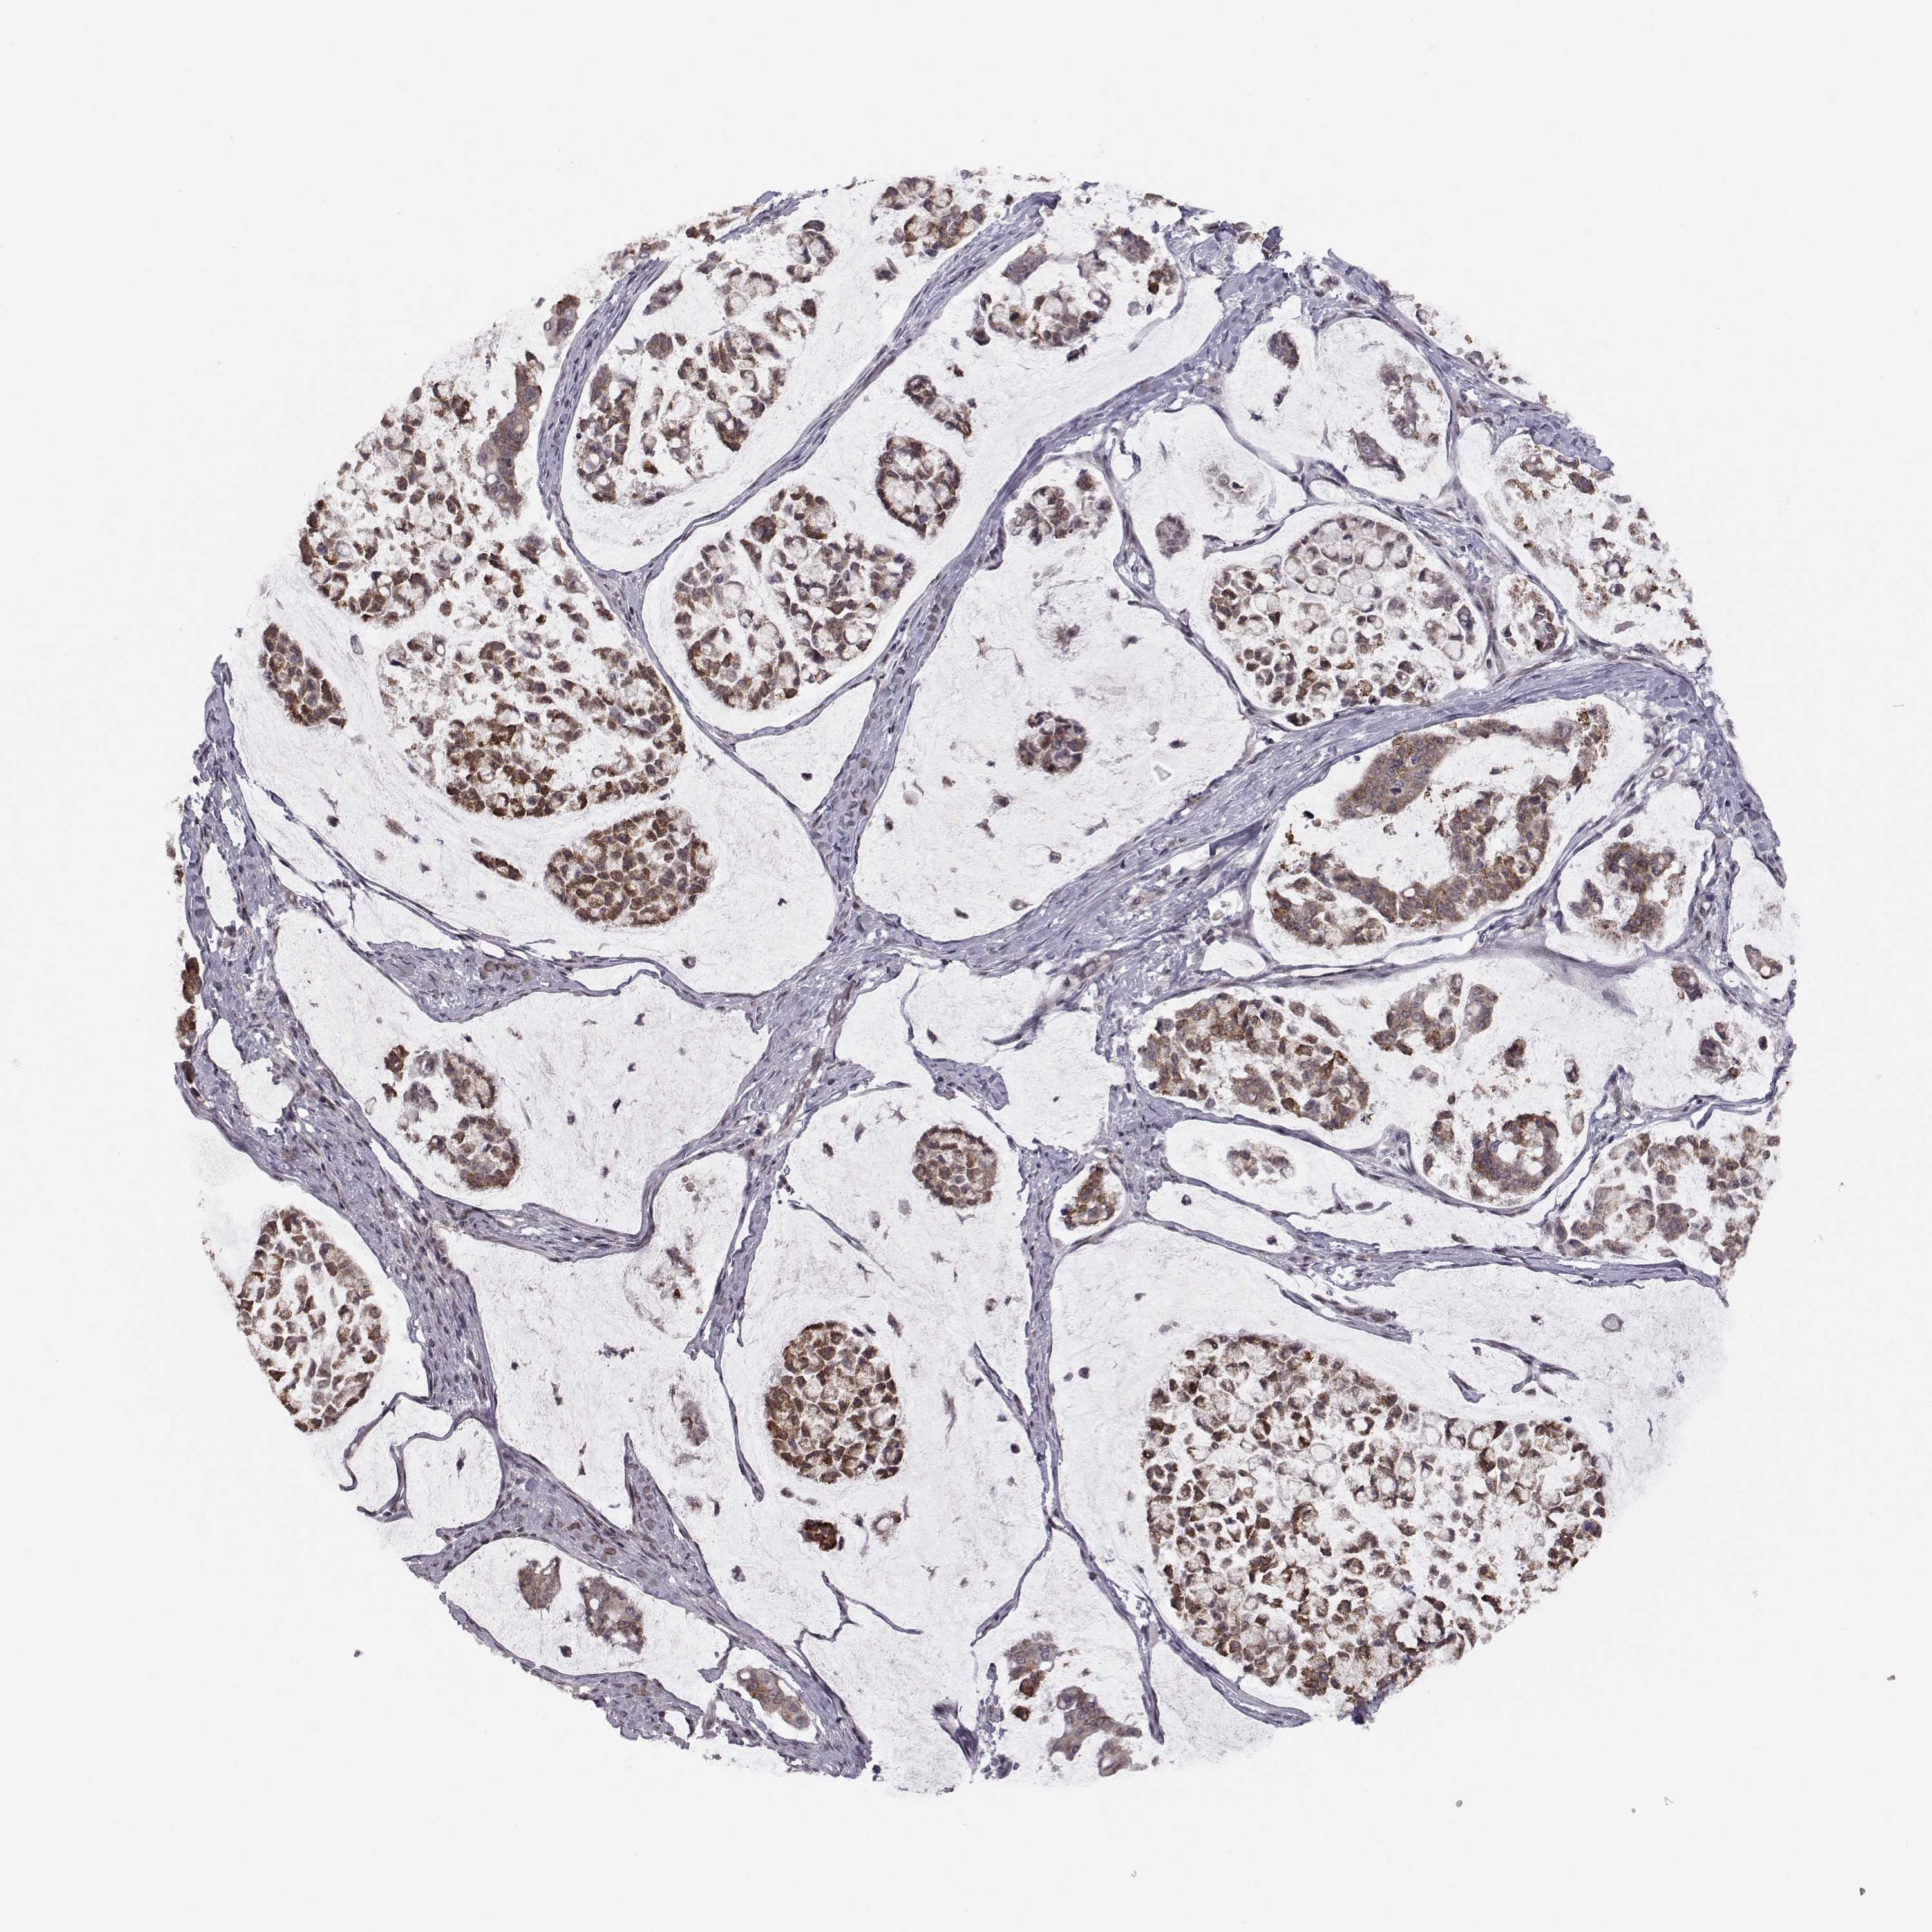

STOMACH CANCER - Protein expressioni

A mouse-over function shows sample information and annotation data. Click on an image to view it in a full screen mode. Samples can be filtered based on level of antibody staining by selecting one or several of the following categories: high, medium, low and not detected. The assay and annotation is described here.

Antibody stainingi

Antibody staining in the annotated cell types in the current human tissue is reported as not detected, low, medium, or high, based on conventional immunohistochemistry profiling in selected tissues. This score is based on the combination of the staining intensity and fraction of stained cells.

Each image is clickable and will lead to virtual microscopy that enables deeper exploration of all samples and also displays staining intensity scores, fraction scores and subcellular localization as well as patient and tissue information for each sample.

Antibody HPA025023

Antibody HPA049655

Staining

High

Medium

Low

Not detected

Intensity

Strong

Moderate

Weak

Negative

Quantity

>75%

75%-25%

<25%

None

Location

Nuclear

Cytoplasmic/membranous

Cytoplasmic/membranous,nuclear

Adenocarcinoma, NOS

Adenocarcinoma, High grade